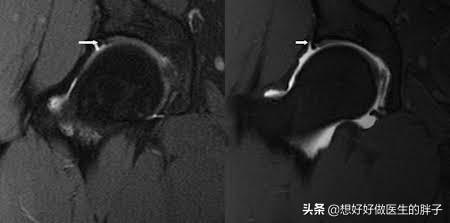

正常的盂唇是比较光滑完整的软骨结构,会完美的包绕在髋臼的周边,负起它应该具有的责任,下图中间的就是正常的盂唇了。

而如果关节发生了撞击综合征,那么盂唇就会发生退变甚至撕裂,大图就是典型的盂唇撕裂的影像学资料,大家可以看到盂唇已经失去了它的完整性,发生了明显的撕裂,这就会导致在关节屈伸的过程当中或者是负重活动的时候出现疼痛。